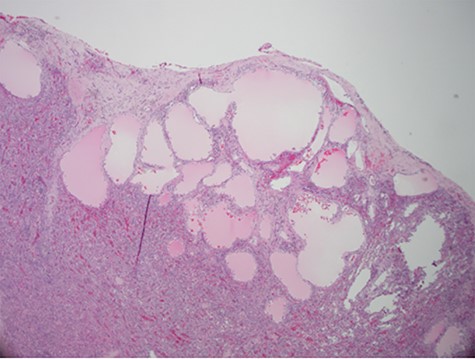

Despite aggressive resuscitation, the patient’s hemodynamics and clinical exam declined. He was taken emergently to the operating room for exploratory laparotomy, evacuation of hemoperitoneum and splenectomy. The spleen was noted to have an isolated nodular, cystic appearing portion in addition to large area of capsular tear. In total, he received four units of PRBC, four units of fresh frozen plasma and one unit of platelets peri-operatively; however, he continued to show signs of hemorrhagic shock. Morning lab-work revealed a Hgb of 5.9 mg/dL from 7.6 mg/dL despite two additional units of PRBC on post-operative day one. Due to continued decline in Hgb and ongoing tachycardia, he returned to the operating room on post-operative days two and four for repeat exploration. Each procedure failed to identify an obvious source of bleeding, except for diffuse oozing in the peritoneal cavity. Further family discussion revealed a history of Hemophilia A in the patient’s brother, diagnosed during childhood. New diagnostic workup was obtained and was consistent with a variant of Hemophilia A. He was subsequently treated with recombinant Factor VIII to a goal of 80–100%, per hematology recommendations, and underwent definitive closure with hemostasis noted on post-operative day six. Pathology report returned as a ruptured spleen with hemorrhage and a subcapsular nodule with dilated lymphovasculature consistent with splenic lymphangioma (Figs 2 and 3).

Hematoxylin and eosin stain photomicrographs from splenectomy consistent with splenic lymphangioma with 10x magnification.